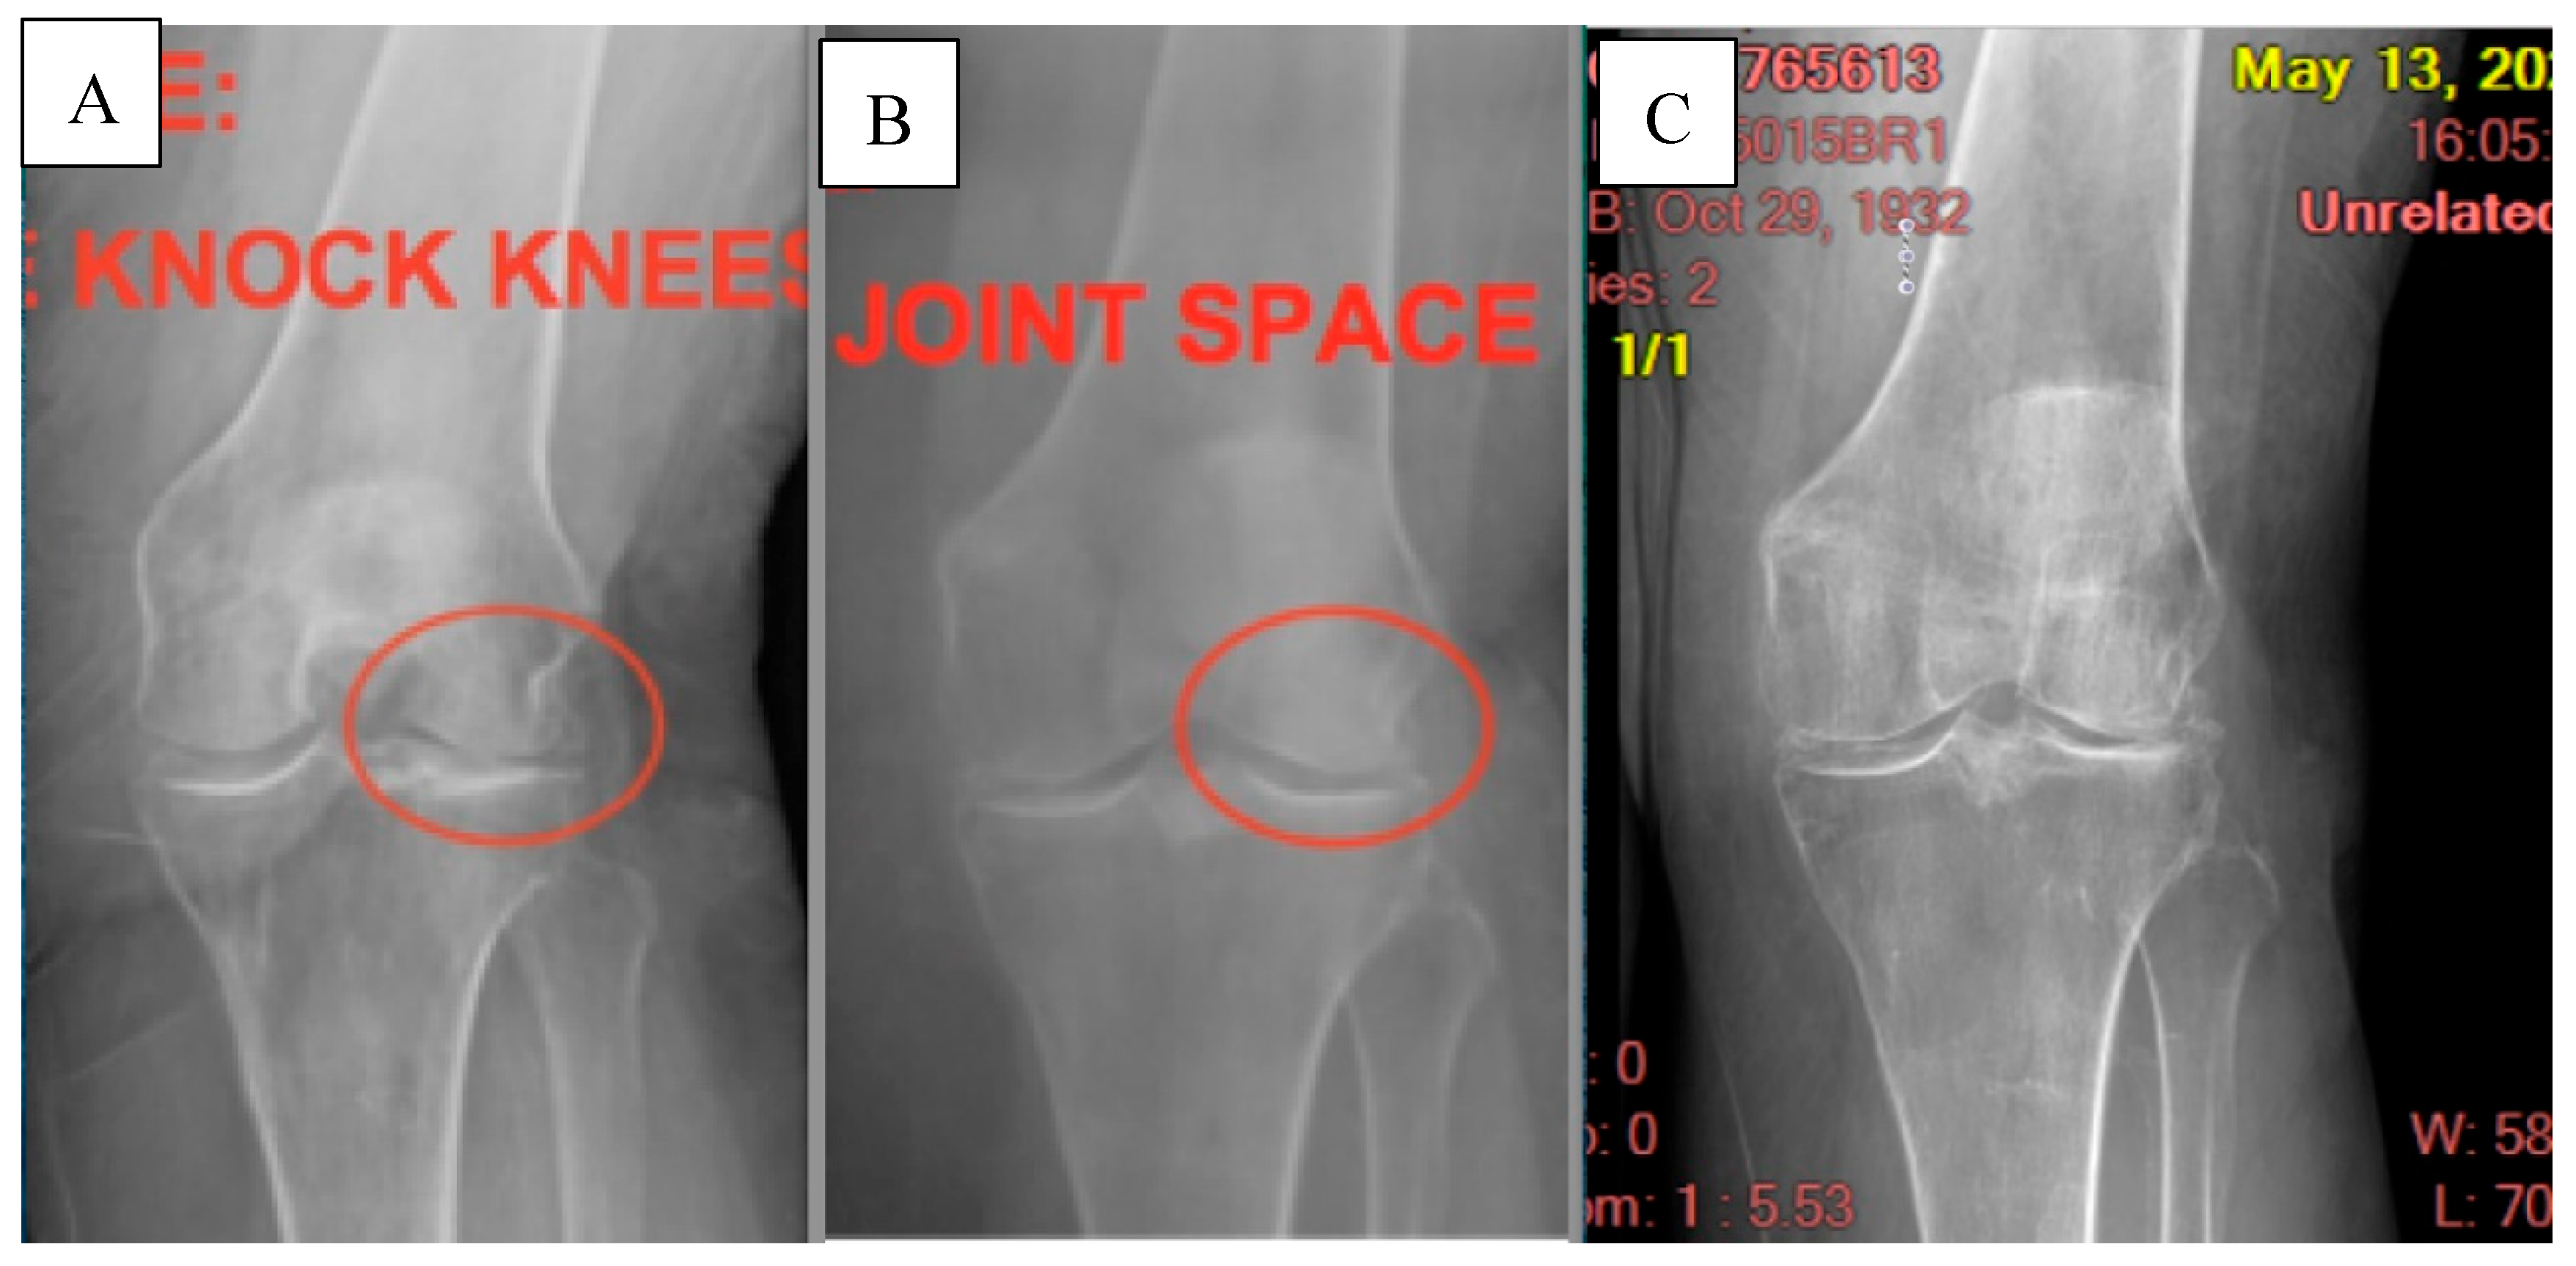

The patient received an initial X-ray on 6/25/18 showing bone-on-bone loss of cartilage space on the lateral side of both knees with genu valgus.

The patient reported a VAS score of 10 at the first visit and a score of 2 one month later at the WJ application visit, but noted little to no functionality improvement. At the three-month visit following the WJ application, the patient reported a 90% pain improvement and an 85% improvement in functionality of the joint. Six months following the WJ application, a follow-up X-ray was conducted, showing improved cartilage space. Twelve months following the WJ application, the patient reported a VAS score of zero. The five-year x-ray shows 50% medial / 100% distal joint space degradation, which is still an improvement from the initial state, but additional WJ tissue supplementation may be beneficial. At the five-year follow-up, the patient reported no pain and had maintained full functionality of the affected knee.

Figure 1. A: The first X-ray taken on 6/25/18 shows bone-on-bone loss of cartilage space. B: The second X-ray taken on 6/26/19, six months after the WJ allograft placement, shows improved cartilage space. C: The final X-ray was taken on 5/13/24 at the five-year follow-up. Some continued degeneration of the cartilage space is shown, but the patient did not experience decreased functionality.